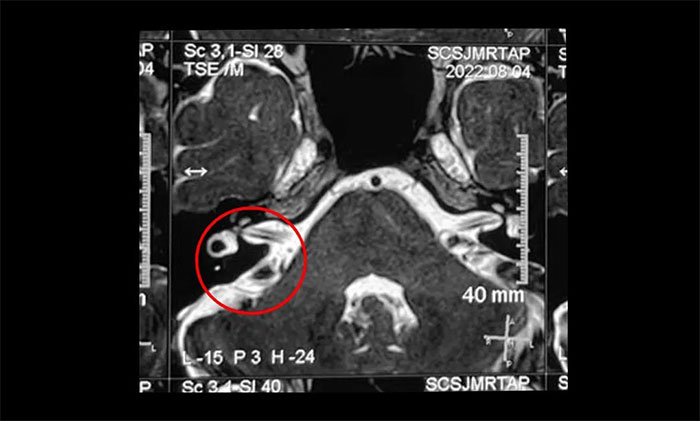

▲ 右側(cè)三叉神經(jīng)與周圍小血管關(guān)系密切

結(jié)合影像資料,楊忠旭教授指出患者右側(cè)三叉神經(jīng)與周圍小血管關(guān)系密切,手術(shù)指征明顯,未見明顯手術(shù)禁忌癥。